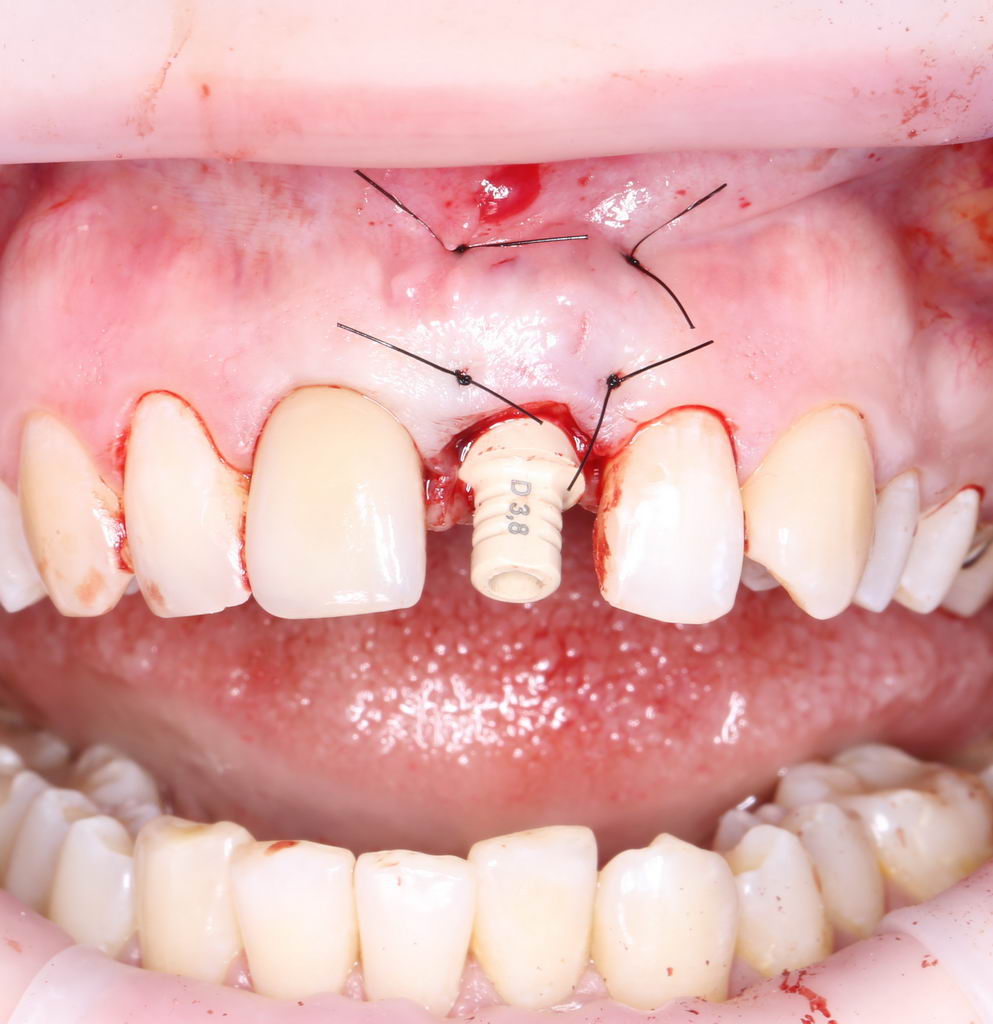

Выглядит это так:

У данной методики есть целый ряд преимуществ — уменьшается время и стоимость стоматологического лечения, результат получается более эстетичным и функциональным за счёт меньшей атрофии альвеолярного гребня и быстрого восстановления нагрузки на участок зубного ряда. Кроме того, нередко мы можем провести полное восстановление зуба (правда, временной реставрацией) в один приём. Благо, все возможности для этого у нас есть.

Вместе с тем, главными минусами немедленной имплантации являются низкая интраоперационная предсказуемость и сильная зависимость от качества удаления зуба. Другими словами, мы принимаем решение об установке имплантата только после того, как зуб удалён, а само качество его установки зависит от того, насколько хорошо мы умеем удалять зубы. Вполне может оказаться, что после удаления, у нас пропадёт возможность установить имплантат — и иногда такое случается. В этом случае, операция заканчивается как обычное удаление, а через 1-2 месяца проводится отсроченная имплантация.